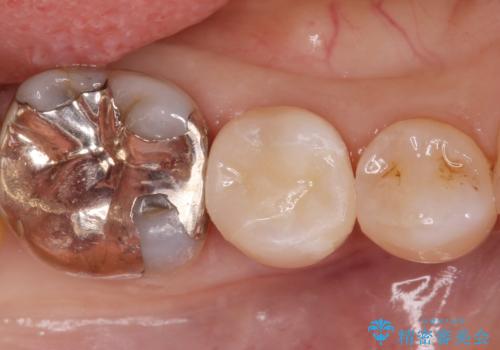

白い詰め物が入り大変満足して頂けました。

現在、奥歯の銀歯も治療を検討中です。